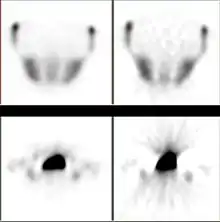

Example showing differences between filtered backprojection (right half) and iterative reconstruction method (left half)

CT scan using iterative reconstruction (left) versus filtered backprojection (right)